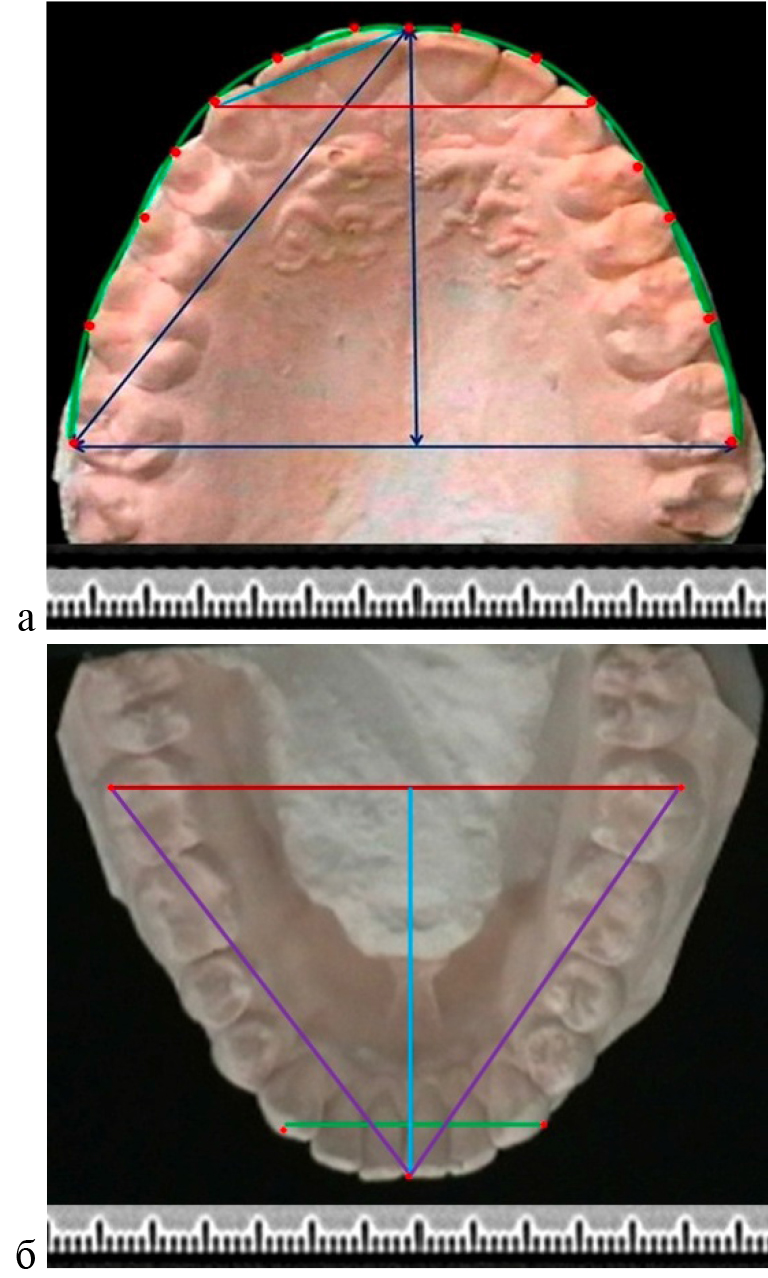

Метод фотостатической биометрии гипсовых моделей челюстей основан на фотографировании моделей с линейкой для удобства последующего масштабирования. На фотографии наносили ориентиры и реперные линии в различных направлениях. Точки для измерения определят исследователь самостоятельно с учетом намеченных задач (рис. 1).

Рис. 1. Фотографии гипсовых моделей верхней (а) и нижней (б) челюсти с нанесенными ориентирами для биометрии и построения геометрических фигур

В соответствии с задачами настоящего исследования на фотографии основным ориентиром была постериальная трансверсаль (ширина между вторыми молярами), которая считается относительно стабильным ориентиром в биометрии зубных дуг. Точка, расположенная на середине указанной линии, позволяла построить условную срединную сагитталь (перпендикуляр) которая при физиологической форме арки проходила между центральными резцами. Диагональные размеры дуги и переднего сектора измеряли от резцовой точки до молярного и клыкового ориентиров.

Углы ротации зубов определяли по отношению к трансверсальной линии зубной арки. При этом условная вестибулярно-лингвальная линия коронки зуба соединяла срединные точки вестибулярного и лингвального окклюзионного контура.

Рис. 2. Фотографии гипсовых моделей верхней (а) и нижней (б) челюсти с нанесенными реперными линиями для определения углов ротации

В исследуемой группе углы ротации вторых моляров составили в среднем (15,01 ± 0,21) градуса на верхней челюсти и (12,49 ± 0,18) градуса на нижней дуге. Первые верхние моляры были ротированы на (19,96 ± 0,22) градуса, а нижние несколько меньше – (17,52 ± 0,16) градуса.